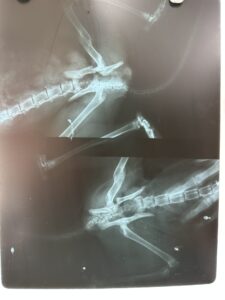

Phía sau bộ phận cần chụp sẽ đặt phim X – quang và máy chụp sẽ chiếu tia X đi xuyên qua cơ thể. Khi tia X gặp phim thì sẽ tạo ra hình ảnh. Nếu càng có nhiều tia X chiếu đến phim thì hình ghi lại càng đen. Do đó, khi nhìn phim, bạn sẽ thấy có những vùng màu trắng. Đó là do những bộ phận cơ thể đặc như xương cản tia X.

Trong khi đó, những phần cơ thể rỗng hoặc đầy khí thì sẽ cho hình ảnh đen. Hình ghi lại tại các mô mềm như các tạng đặc hoặc cơ trong cơ thể thường có màu xám. Mức độ màu xám sẽ phụ thuộc vào độ đậm đặc của các bộ phận. Kỹ thuật chụp tia X cần được thực hiện trong môi trường an toàn. Từ các hình ảnh đó, các bác sĩ sẽ đọc phim X – quang và chẩn đoán.